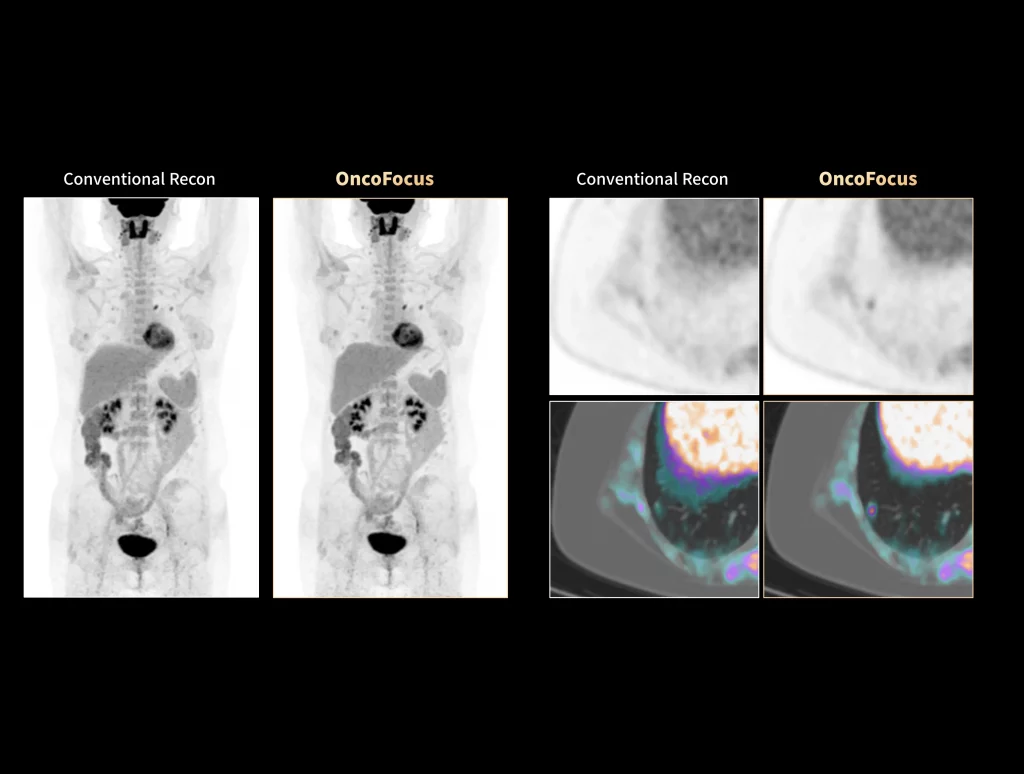

uMI Panorama is greatly empowered by innovative technologies integrated into the uExcel SCAN and uExcel CARE workflows. With uExcel SCAN, you can rely on intelligent positioning, scanning, and motion correction to streamline your routine tasks and maximinze your work efficiency. And uExcel CARE features uExcel DPR and uExcel AIIR reconstruction algorithms to ensure clear images even at low doses.